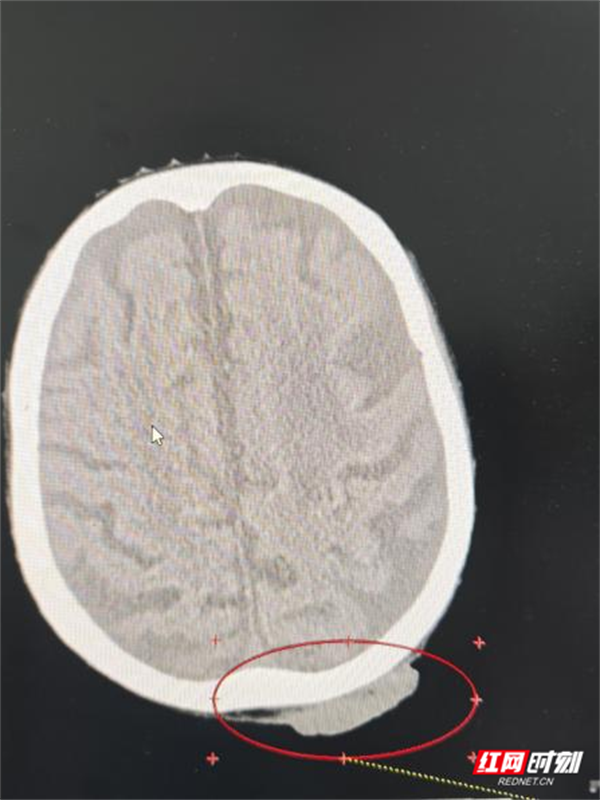

医生为谭奶奶进行了头部MRI等详细检查后,确诊她患“头皮恶性肿瘤鳞癌Ⅲ期”。这一结果让她和家人的心情跌落谷底——在他们看来,肿瘤本身就是难以治愈的疾病,更何况高龄老人还伴有多种基础疾病。